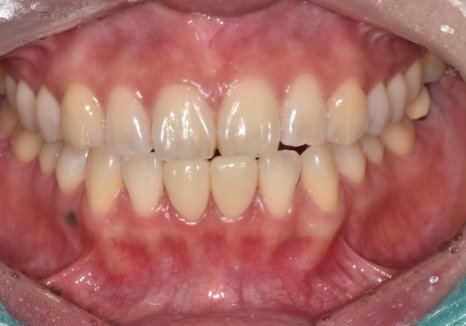

250313 (전) 250318 (후)

튀어나온 부분을 살짝 다듬고 표면을 처리하는 과정은 필요할 수밖에 없습니다.

대부분의 경우 치아 전체를 깎는 게 아니라

필요한 부분만 선택적으로 삭제하는

최소 삭제 방식이 권장됩니다.